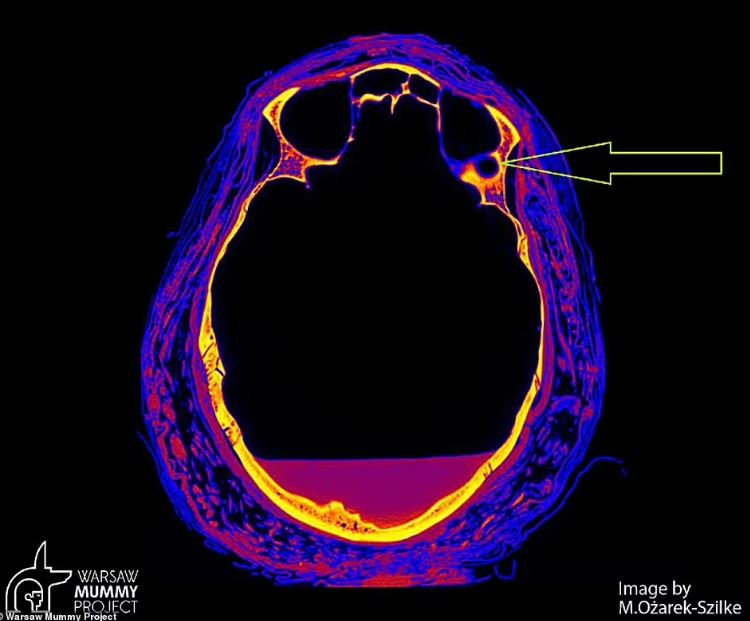

به گزارش تازهنیوز، اسکن های یک مطالعه جدید نشان می دهند که جسد ۲۰۰۰ ساله اولین مومیایی باردار مصر باستان مبتلا به سرطان بوده و احتمالاً در اثر یک نوع نادر از این بیماری در هفته ۲۸ بارداری مرده است. محققان لهستانی در حال انجام اسکن از جمجمه جسد باستانی بودند که علائم غیرعادی ای را در استخوانش کشف کردند. با توجه به اینکه، علائم مشاهده شده، مشابه آنچه در بیماران مبتلا به سرطان نازوفارنکس است، دانشمندان به این نتیجه رسیدند که این مومیایی به احتمال زیاد در اثر همان بیماری مرده است. سرطان نازوفارنکس نوع نادری از سرطان است که قسمتی از گلو را که پشت بینی را به پشت دهان وصل می کند، درگیر می کند. محققان قبلا می دانستند که این زن، ملقب به «بانوی اسرار آمیز» در هفته ۲۸ بارداری خود مرده بود، اما اکنون آنها علت مرگ او را مشخص کردهاند.

سال گذشته در معاینه ای با استفاده از تصویربرداری توموگرافی مشخص شد که این زن بین ۲۰ تا ۳۰ سال سن داشته و در هفته ۲۶ تا ۳۰ بارداری خود بوده است. به گفته نویسندگانی که در مجله علوم باستان شناسی می نویسند، جسد با دقت در پارچه ها پیچیده شده بود و با مجموعه ای غنی از تعویذها برای دیدار او در زندگی پس از مرگ همراه بود.